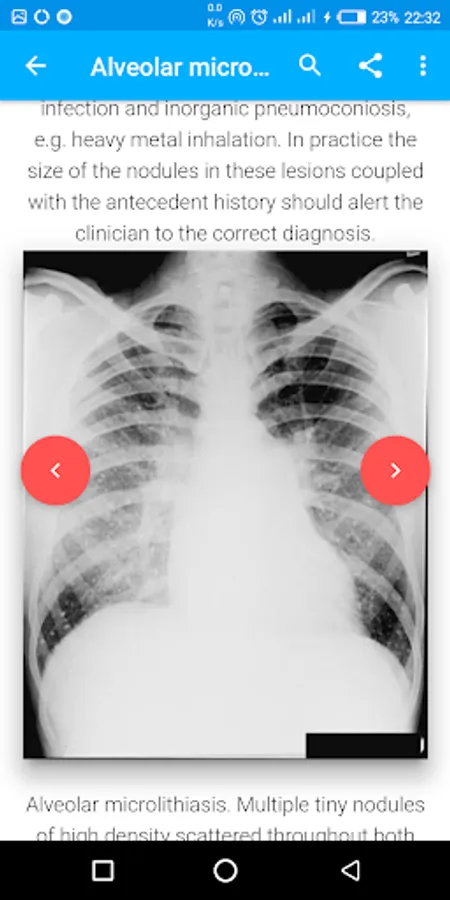

This Application contains a detailed discussion of many chest disorders (Pathology), definitions, listing appearances, differential diagnoses, clinical features, radiological advice, and management.

Each Pathology is highly described to aid diagnosis and the management advice is concise and practical.